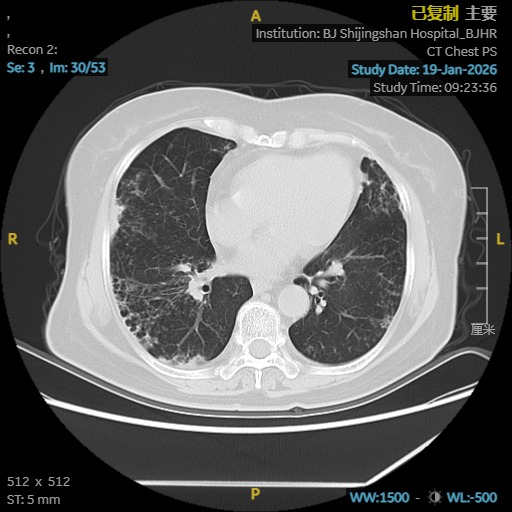

依托医院高清CT、肺功能、气管镜及精准分子检测平台,团队很快锁定了隐藏在表象背后的真实病因:鸟胞内分枝杆菌合并耐药念珠菌感染,同时伴有进展性肺间质纤维化。这两种疾病相互交织,诊治难度大,对医疗团队提出了很高要求。

为给患者制定最安全有效的治疗方案,马霞主任医师立即启动MDT机制,联合临床药师、影像科、检验科专家进行会诊。在多学科共同研判下,团队为栗女士量身定制了集抗感染、抗真菌、抗纤维化于一体的综合治疗策略,在精准打击病原的同时,全力保护肺功能。

A影像学证据:胸部高分辨率CT(HRCT)显示存在肺纤维化表现,如网格影、蜂窝影、牵拉性支气管扩张等,且排除特发性肺纤维化(IPF)。